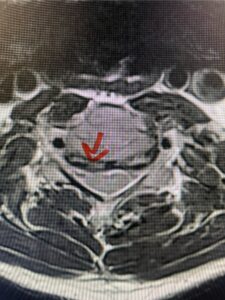

This 61-year-old female with a history of severe osteoporosis and a prior history of a laminectomy from l2-S1 with an L5-S1 instrumented fusion, presents with progressive low back pain and right lower extremity radiculopathy. MRI revealed a grade 1 L2-3 spondylolisthesis with severe stenosis mainly from severe right L2-3 facet joint hypertrophy which was compressing the right L3 descending nerve root. (Fig. 1). She had failed conservative management consisting of physical therapy and pain management with epidurals. She underwent an L1-3 revision laminectomy where we had to dissect a plane underneath the inferior aspect of the L2 lamina. We performed an instrumented fusion at L2-3 with special hydroxyapatite-coated screws to improve fixation to surrounding bone given here severe osteoporosis (Fig. 2) This worked out well and the patient had an uneventful recovery with relief of her leg pain.

Figures 1a: Sagittal and axial T2-weighted lumbar MRIs demonstrating a grade 1 L2-3 spondylolisthesis (red arrow) with severe stenosis secondary to right L2-3 facet hypertrophy (red arrow).

Fig 1b: Note the left L2-3 facet joint (blue arrow) is normal in size compared to the right (red arrow)